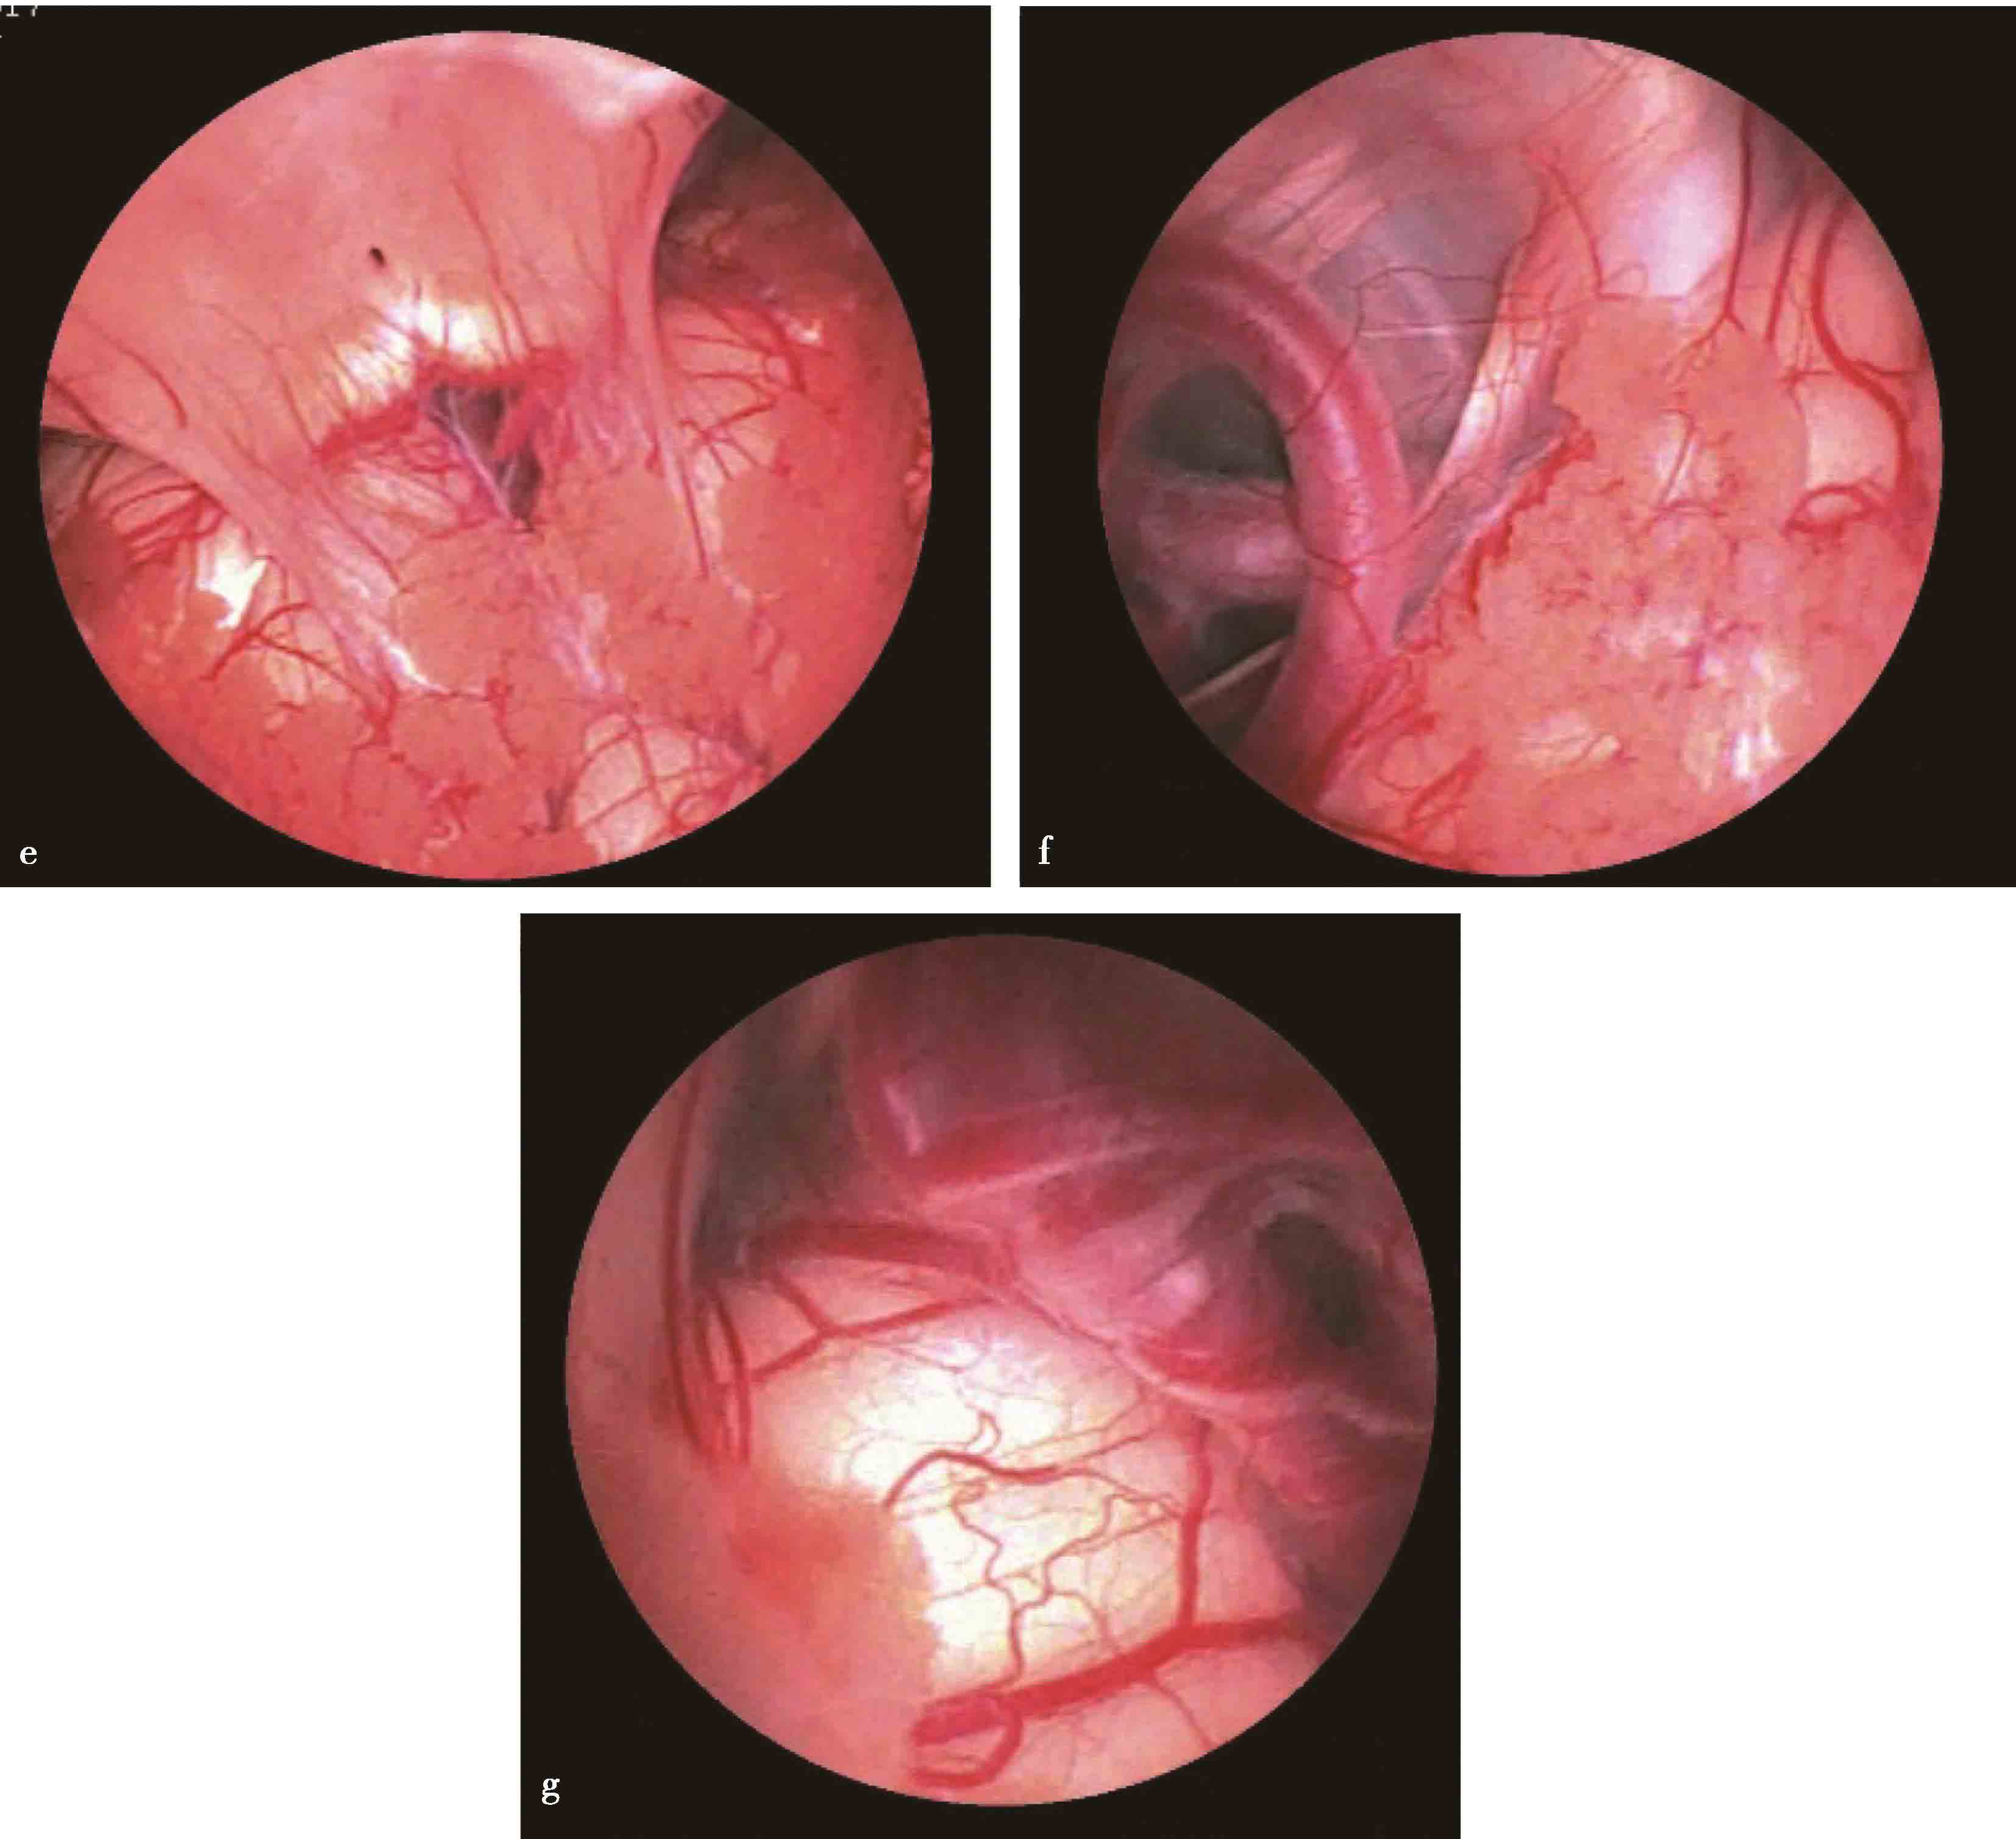

图3-1-1-4 感染后脑积水内镜下探查所见

a.脑室壁上的菌斑;b.脑室内结核所致干酪样坏死物;c.脑室内真菌感染;d.第四脑室内囊虫

2.单侧或双侧室间孔狭窄或闭塞所致一侧或双侧侧脑室积水,采用内镜下室间孔成形术进行治疗(图3-1-2-1)。

图3-1-2-1 室间孔狭窄的影像学表现

a.右侧室间孔狭窄,头颅MRI轴位;b.右侧室间孔狭窄,头颅MRI冠状位;c.左侧室间孔狭窄,头颅MRI轴位;d.双侧室间孔狭窄,头颅MRI冠状位;e.内镜下可见左侧室间孔闭塞、右侧室间孔狭窄;f.内镜下可见左侧室间孔闭塞;g.内镜下可见右侧室间孔闭塞;h.室间孔球囊成形;i.经球囊成形后的室间孔